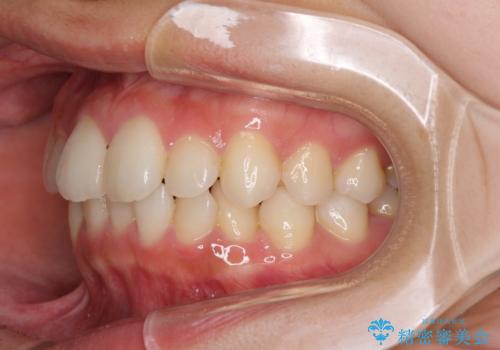

- 前歯のデコボコを気にして来院された患者様です。

叢生と捻転が随所に認められるものの、マウスピースで十分対応可能であったため、インビザラインにて矯正治療を行うこととしました。

マウスピース矯正は毎日しっかりと装着することがとても大切です。

こちらの方はしっかりと指示を守って装着してくださったため、予定通り治療を終えることができました。